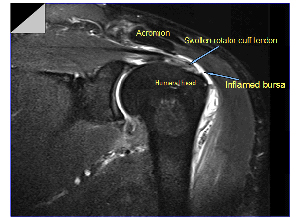

There is a lubricating sac called a bursa between the rotator cuff and the bone on top of your shoulder (acromion). The bursa allows the rotator cuff tendons to glide freely when you move your arm.

Impingement is a condition where in the rotator cuff or bursa or both rub (impinge) underneath the acromion. It is a common source of pain in the shoulder. Three common reasons for impingement include:

Magnetic resonance imaging (MRI) and ultrasound. These studies can create better images of soft tissues like the rotator cuff tendons. They can show fluid or inflammation in the bursa and rotator cuff. In some cases, partial tearing of the rotator cuff will be seen.

These studies can create better images of soft tissues like the rotator cuff tendons. They can show fluid or inflammation in the bursa and rotator cuff. In some cases, partial tearing of the rotator cuff will be seen.